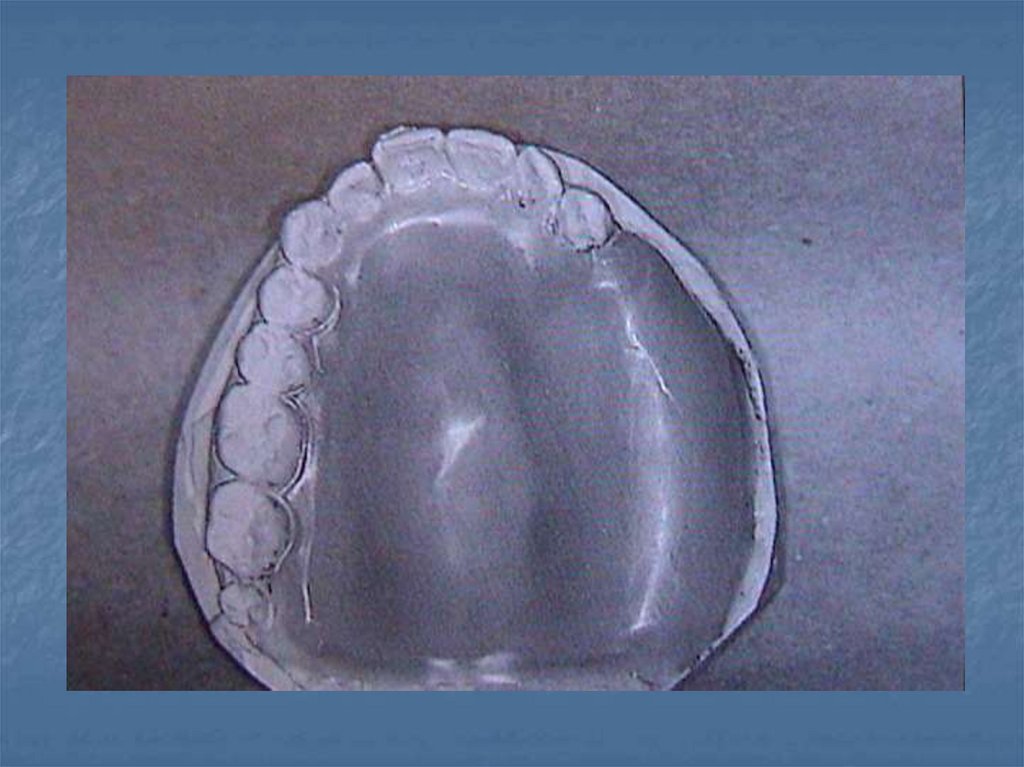

54. Daimi obtüratörler

Ameliyattan 8-12 hafta sonra uygulanan

protezlerdir.protez için gerekli bütün

ayrıntıları taşırlar.

Bu protezlerden sonra hasta ışın tedavisine

tabi tutulursa protezle dokuların uyumu

bozulacağından daimilik özelliği kaybolur.